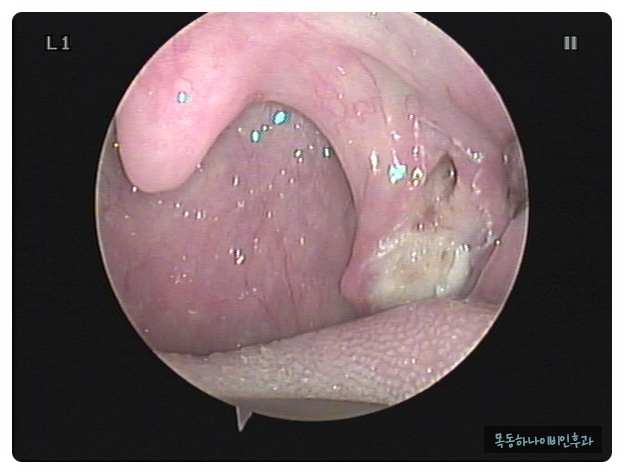

편도결석은 눈으로 확인하면 바로 진단이 가능합니다. 양치질이나 기침을 할 때 튀어나오거나 눈에 보이는 경우도 있습니다. 증상은 있지만 눈으로 관찰되지 않을 때 병원에서 후두 내시경으로 목 안쪽에서 관찰될 수도 있습니다.